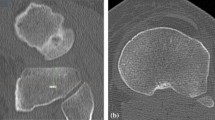

On the tibial side, each evaluator created three axes: the axis across the greatest medial to lateral width of the tibial plateau (ML), the posterior tibial condylar axis (PC), and the axis perpendicular to the line connecting the midpoint of the greatest mediolateral dimension of the tibial slice being evaluated to the medial 1/3 of the tibial tubercle (TUB) (Figs. 1, 2). Because the tibial tubercle was not always visible on the MR slices evaluated, the patellar tendon was used as a surrogate for the tibial tubercle in these slices. The PCL insertion was not used as the posterior point on this line as the PCL insertion disappears at the more distal resection levels.

A box and whiskers plot incorporating the measurements of all three observers is shown. The vertical axis represents the difference in degrees between the position of the measured axis and the reference femoral epicondylar axis. The line in the box denotes the median value, the upper and lower ends of the box span the central half of all the values, and the whiskers indicate the range of values. The TUB axis was the most accurate across all resection levels, but the ranges, as spanned by the error bars, were smallest with the PC axis. ML is the axis defined by the greatest mediolateral dimension of the tibial surface. PC is the posterior tibial condylar axis. TUB is the axis connecting the geometric center of the tibial plateau with the medial 1/3 of the tibial tubercle. Resection levels are 6–8 mm below the tibial surface, and the proximal (P), middle (M), and distal (D) levels of the proximal tibiofibular joint.

Each of these three axes was identified at four different levels on the proximal tibia, as referenced by the coronal scout images on the computer workstation. The proposed resection levels were between 6 and 8 mm below the joint, the proximal tibiofibular joint, the middle aspect of the tibiofibular joint, and the distal aspect of the proximal tibiofibular joint. The first resection level is a standard amount in a primary TKA, and the latter resection levels are more distal resection levels frequently required in complex primary or revision TKA. We chose to reference the more distal resection levels to the tibiofibular joint rather than measuring standard distances below the native joint line because the original level of the joint line is not commonly known in the revision setting, and because standard distances would be proportionally larger or smaller resections based on the patient’s bone size. The proximal tibiofibular joint usually is preserved in the revision setting and provides a reasonable landmark for depth of tibial resection.

The ML dimension of the tibia was characterized as the widest point across the tibial plateau at each resection level. The PC axis was a line formed connecting the posterior margins of the medial and lateral tibial condyles. The axis relative to the patellar ligament insertion was created by first identifying the center point of the ML axis on the tibial plateau and then creating a line to the medial 1/3 mark of the tibial tubercle, or the patellar tendon when the tubercle was not visible on the slice. The TUB axis was the perpendicular to this line. For each observer, 12 data points were collected on each MR image of the knee (three axes at each of four different resection levels), with negative numbers correlating to internal rotation relative to the reference femoral TEA and positive numbers correlating to external rotation.

The data, as averaged for the three observers, were summarized in a box and whiskers plot (Fig. 1). For each rater, at all resection levels, the average ML and PC axes were internally rotated relative to the TEA, and the TUB axis was neutral or externally rotated. As the resection level moved distally, each of these axes, on average, deviated farther from the reference TEA axis (Fig. 2). The TUB axis, on average, was nearest to the TEA at all resection levels. Even at the aspect of the distal tibiofibular joint, the mean TUB axis was externally rotated only 5° from the reference TEA. Thus across all raters, and at all resection levels, the TUB axis was, on average, the most accurate indicator of the location of the transposed femoral epicondylar axis.

The most precise axis, however, was the PC axis. Across all raters and all resection levels distal to the standard level, the standard deviation of the measured axis position was lowest for the PC axis. Equality of variance testing confirmed that the PC axis had less variance than the ML and TUB axes, particularly as resection levels moved distally (Table 1). In addition, the range of axis alignment with the PC axis was the smallest of the three axes tested across all resection levels.